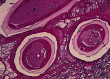

Fig 1.

Histological section of a nodule showing the worm and surrounding tissue excised from the patient. Morphological characteristics of the female worm identified as Onchocerca dewittei japonica showing the salient transverse ridges (arrows), lateral chords (*), uteri (U), and intestine (I). The section is stained with hematoxylin and eosin. Bar, micrometers.